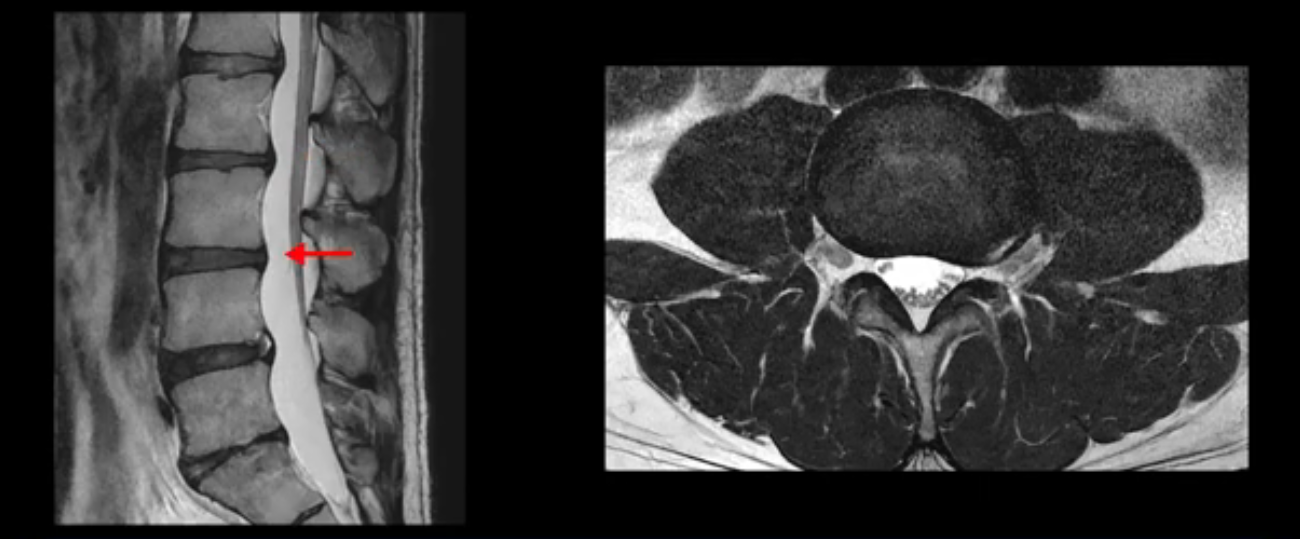

우선 이분 MRI를 보면 허리 모든 마디의 디스크가 퇴행되어 있고

여러 마디의 디스크가 조금씩 밀려나와 보이고, 디스크 섬유륜도 찢어져 보이는 마디도 보입니다.

그런데 이분의 증상과 MRI가 전혀 일치하지 않는데, 왜 그런지 지금부터 자세히 설명드립니다. 이분 증상은 앉으면 엉치와 허리가 심하게 아파 10분 이상 앉는 게 어렵고 양쪽 발가락이 앉아있을 때나 누워있을 때 다 저립니다. 걸을 때도 아파서 10분 걷기도 어렵습니다. MRI를 마디마디 살펴보면 1번 2번은 오른쪽으로 살짝 밀려나온 디스크가 있지만 전혀 심하지 않고, 뒤에 또 설명하겠지만 최근에 밀려나온 급성 디스크가 아니고 오래된 디스크로 판단됩니다.

2번 3번도 비교적 디스크 상태는 좋고 신경 구멍 넓이도 아주 넓습니다.

3번 4번도 마찬가지로 디스크상태 좋아 보이고 신경 눌림 전혀 없어 보입니다.

4번 5번은 가운데로 섬유륜이 찢어져서 디스크가 살짝 밀려나와 있지만 역시나 최근에 찢어지고 밀려나온 걸로 판단되지 않고 오래 전에 찢어진 흔적으로 보입니다.

왜 최근에 찢어진 급성이 아니고 오래된 거라고 하는지 이 부분도 뒤에 한꺼번에 설명 드리겠습니다.

5번 1번 역시 가운데로 디스크 조금 밀려 나와있지만 신경 공간 넓이는 아주 넓어서 신경 눌림 있을 거라고 예상이 안됩니다.